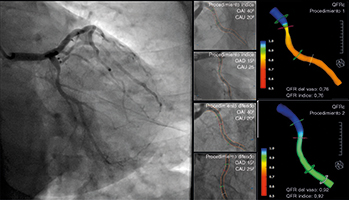

Cambios QFR a lo largo de los procedimientos índice y diferido

Ciento veintidós (93,1%) de las 131 lesiones en vasos no causantes se consideraron aptas para ser sometidas a revascularizaciones percutáneas programadas según valoración visual de la angiografía. De estas, solo el 56,3% arrojaron valores QFR ≤ 0,80 en el procedimiento índice cuando se valoraron retrospectivamente (figura 3). Se pudo confirmar una caída sin relevancia estadística de los valores QFR entre el procedimiento índice y el diferido en pacientes con valores QFR iniciales > 0,80; no obstante, 2 pacientes con valores QFR inicialmente irrelevantes experimentaron una caída < 0,80 en la valoración de la angiografía diferida. Todos los pacientes con valores iniciales > 0,82 confirmaron la presencia de estenosis en el segundo procedimiento. Por otro lado, el 45,9% de las lesiones con valores QFR significativos fueron consideradas irrelevantes cuando fueron valoradas durante el segundo procedimiento, con diámetros medios y áreas estenóticas más grandes (p < 0,001 para ambos) tal y como revela la tabla 2. Los principales cambios observados entre ambos procedimientos se muestran en la figura 4 y en el ejemplo paradigmático de la figura 5. La sensibilidad y especificidad de valores QFR > 0,82 durante el procedimiento índice para predecir estenosis importantes (QFR < 0,80) durante el procedimiento programado fueron del 84 y 58,7%, respectivamente, con un valor predictivo positivo del 52,5% y un valor predictivo negativo del 87% (figura 6). La estrategia terapéutica se implementó con independencia de los hallazgos de la valoración de QFR ya que se hizo una estimación de ésta retrospectivamente. Esto nos permitió comparar la estrategia en base a la interpretación de la valoración de la angiografía visual y posteriores hallazgos QFR en un total de 46 lesiones tratadas con stents a pesar de presentar valores QFR irrelevantes.

Figura 5. Cambios en los valores QFR para la arteria circunfleja durante los procedimientos índice y diferido en paciente con IAMCEST inferior secundario a una oclusión en la coronaria derecha. IAMCEST: infarto agudo de miocardio con elevación del segmento ST; QFR: ratio de flujo cuantitativo.